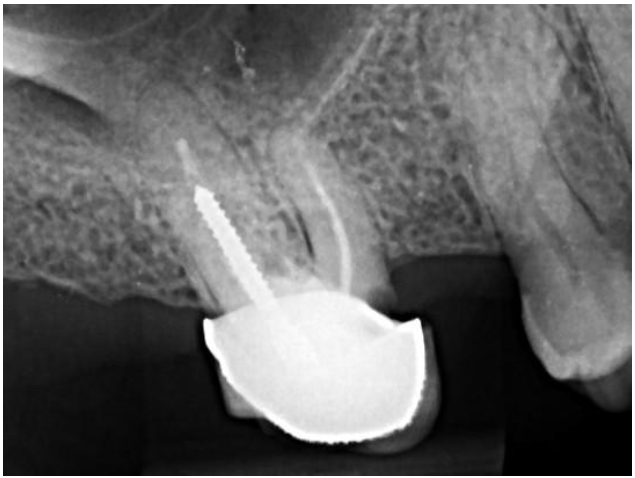

Image after compacting gutta-percha

Glass fiber post

Radiograph after performing the retreatment